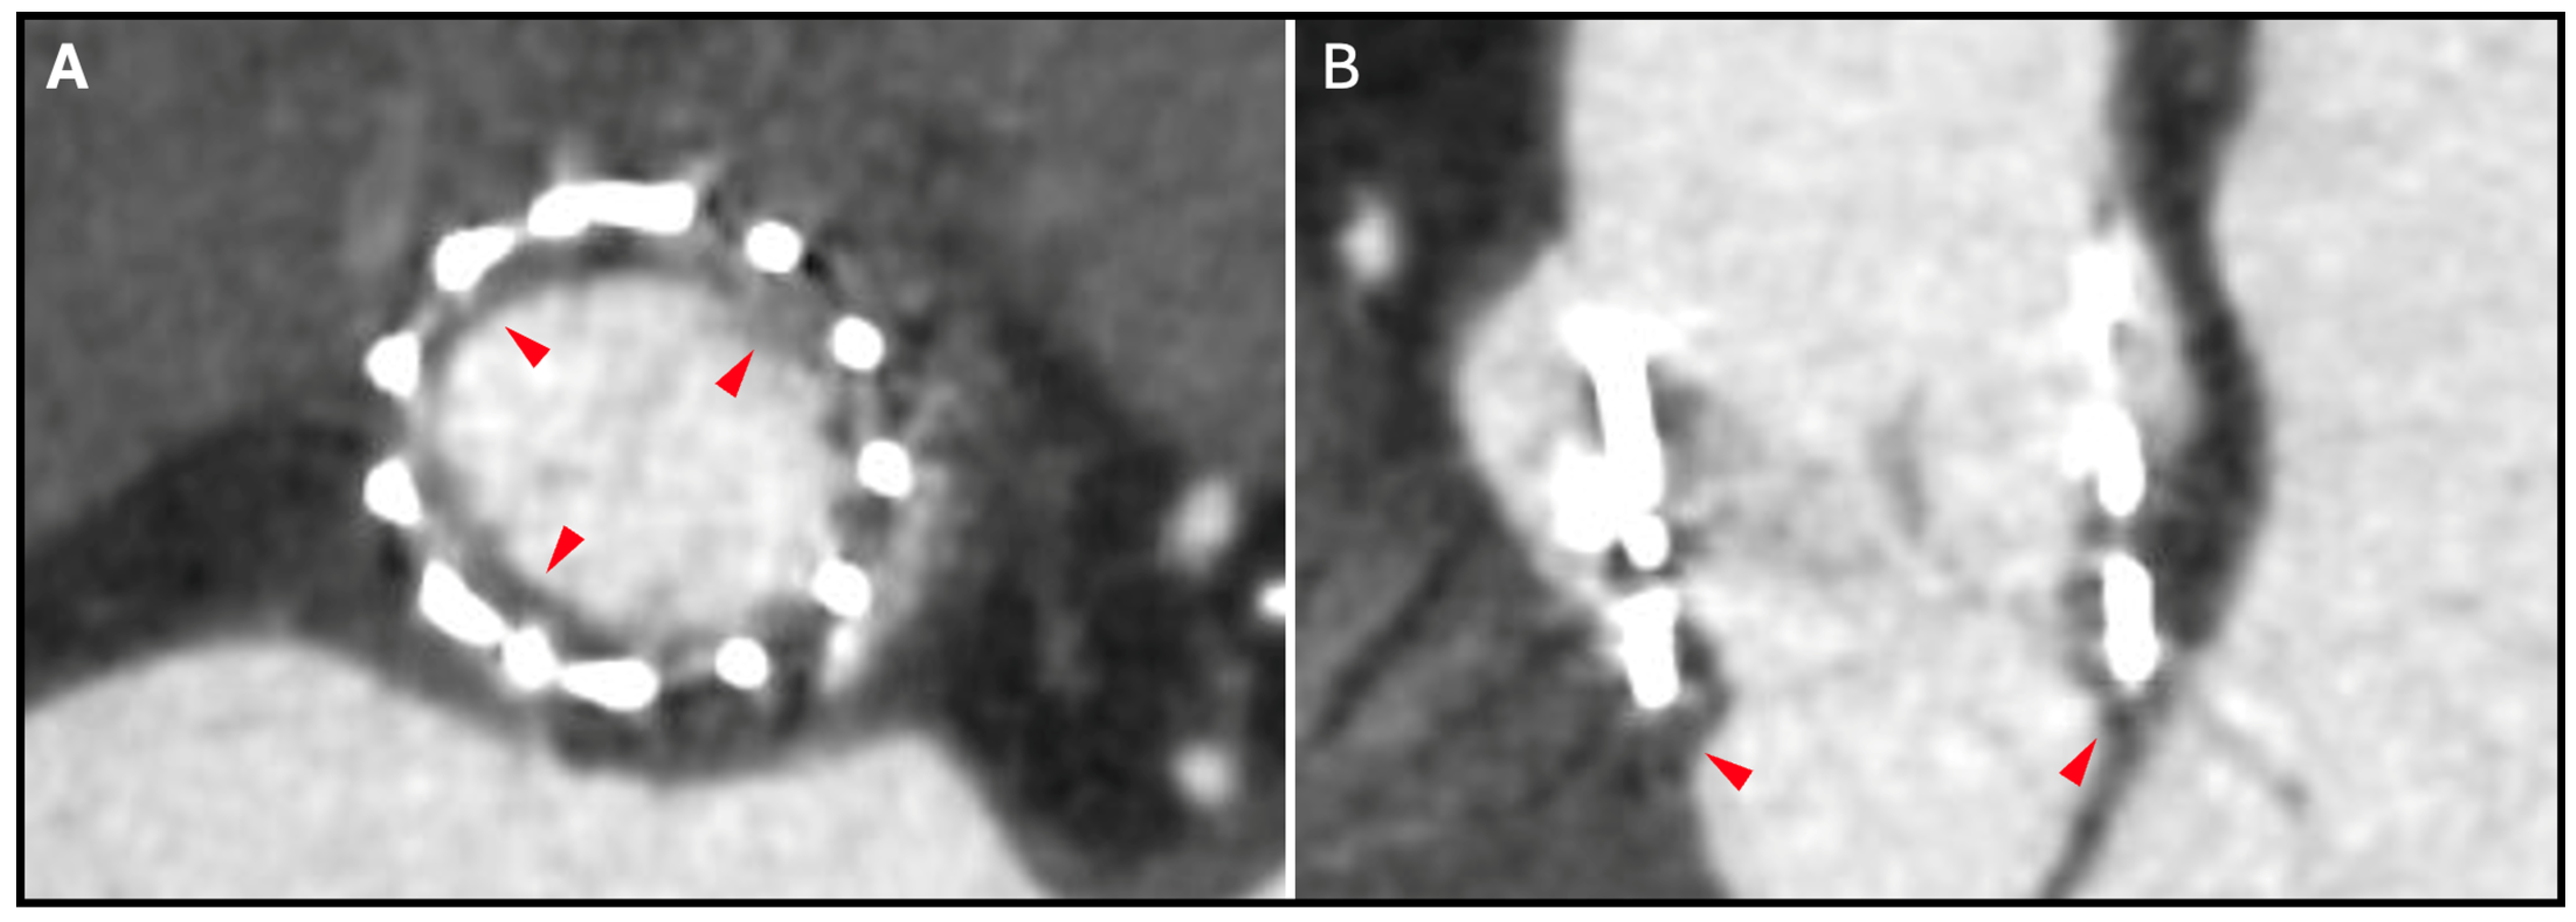

13. THV Underexpansion